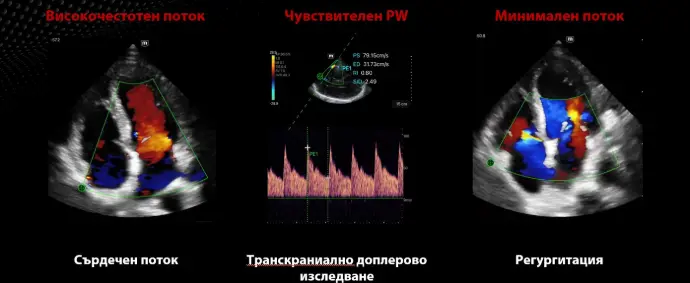

Спешна медицина

FAST/eFAST, фокусирани сърдечни, коремни, транскраниални и основни белодробни

Работа в отделението, консултация: сърдечна, белодробна, FAST/eFAST, оценка на обема, TCI

Кардиология

Бърза диагностика на сърдечната функция; скрининг за сърдечна патология

Клинични снимки